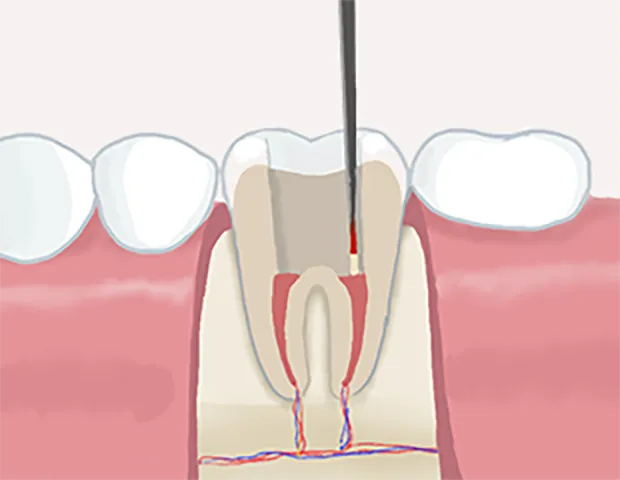

根管治療とは歯の根っこにある歯髄と呼ばれる神経や血管が通っている細い管状の部分である根管の中にある「虫歯に感染した歯の神経」「細菌」「過去に詰めた古い充填材」等を除去していく治療法です。細菌に侵された部分を丁寧に除去・消毒・洗浄を行い、薬液を充填して歯を温存します。

根管治療の流れ

1虫歯の除去

虫歯になった部分を取り除き、歯の神経があるところまで穴をあけます

• 神経の除去

2神経の除去

細菌が侵入し変質してしまった神経を除去し、神経の通っている穴と根の中の管をきれいに清掃します。

• 根管内の洗浄

3根管内の洗浄

根管内を薬液で洗浄消毒して、細菌を隅々まで取り除きます。

• 薬剤充填

4薬剤充填

薬液を充填し、細菌が繁殖しないようにします。